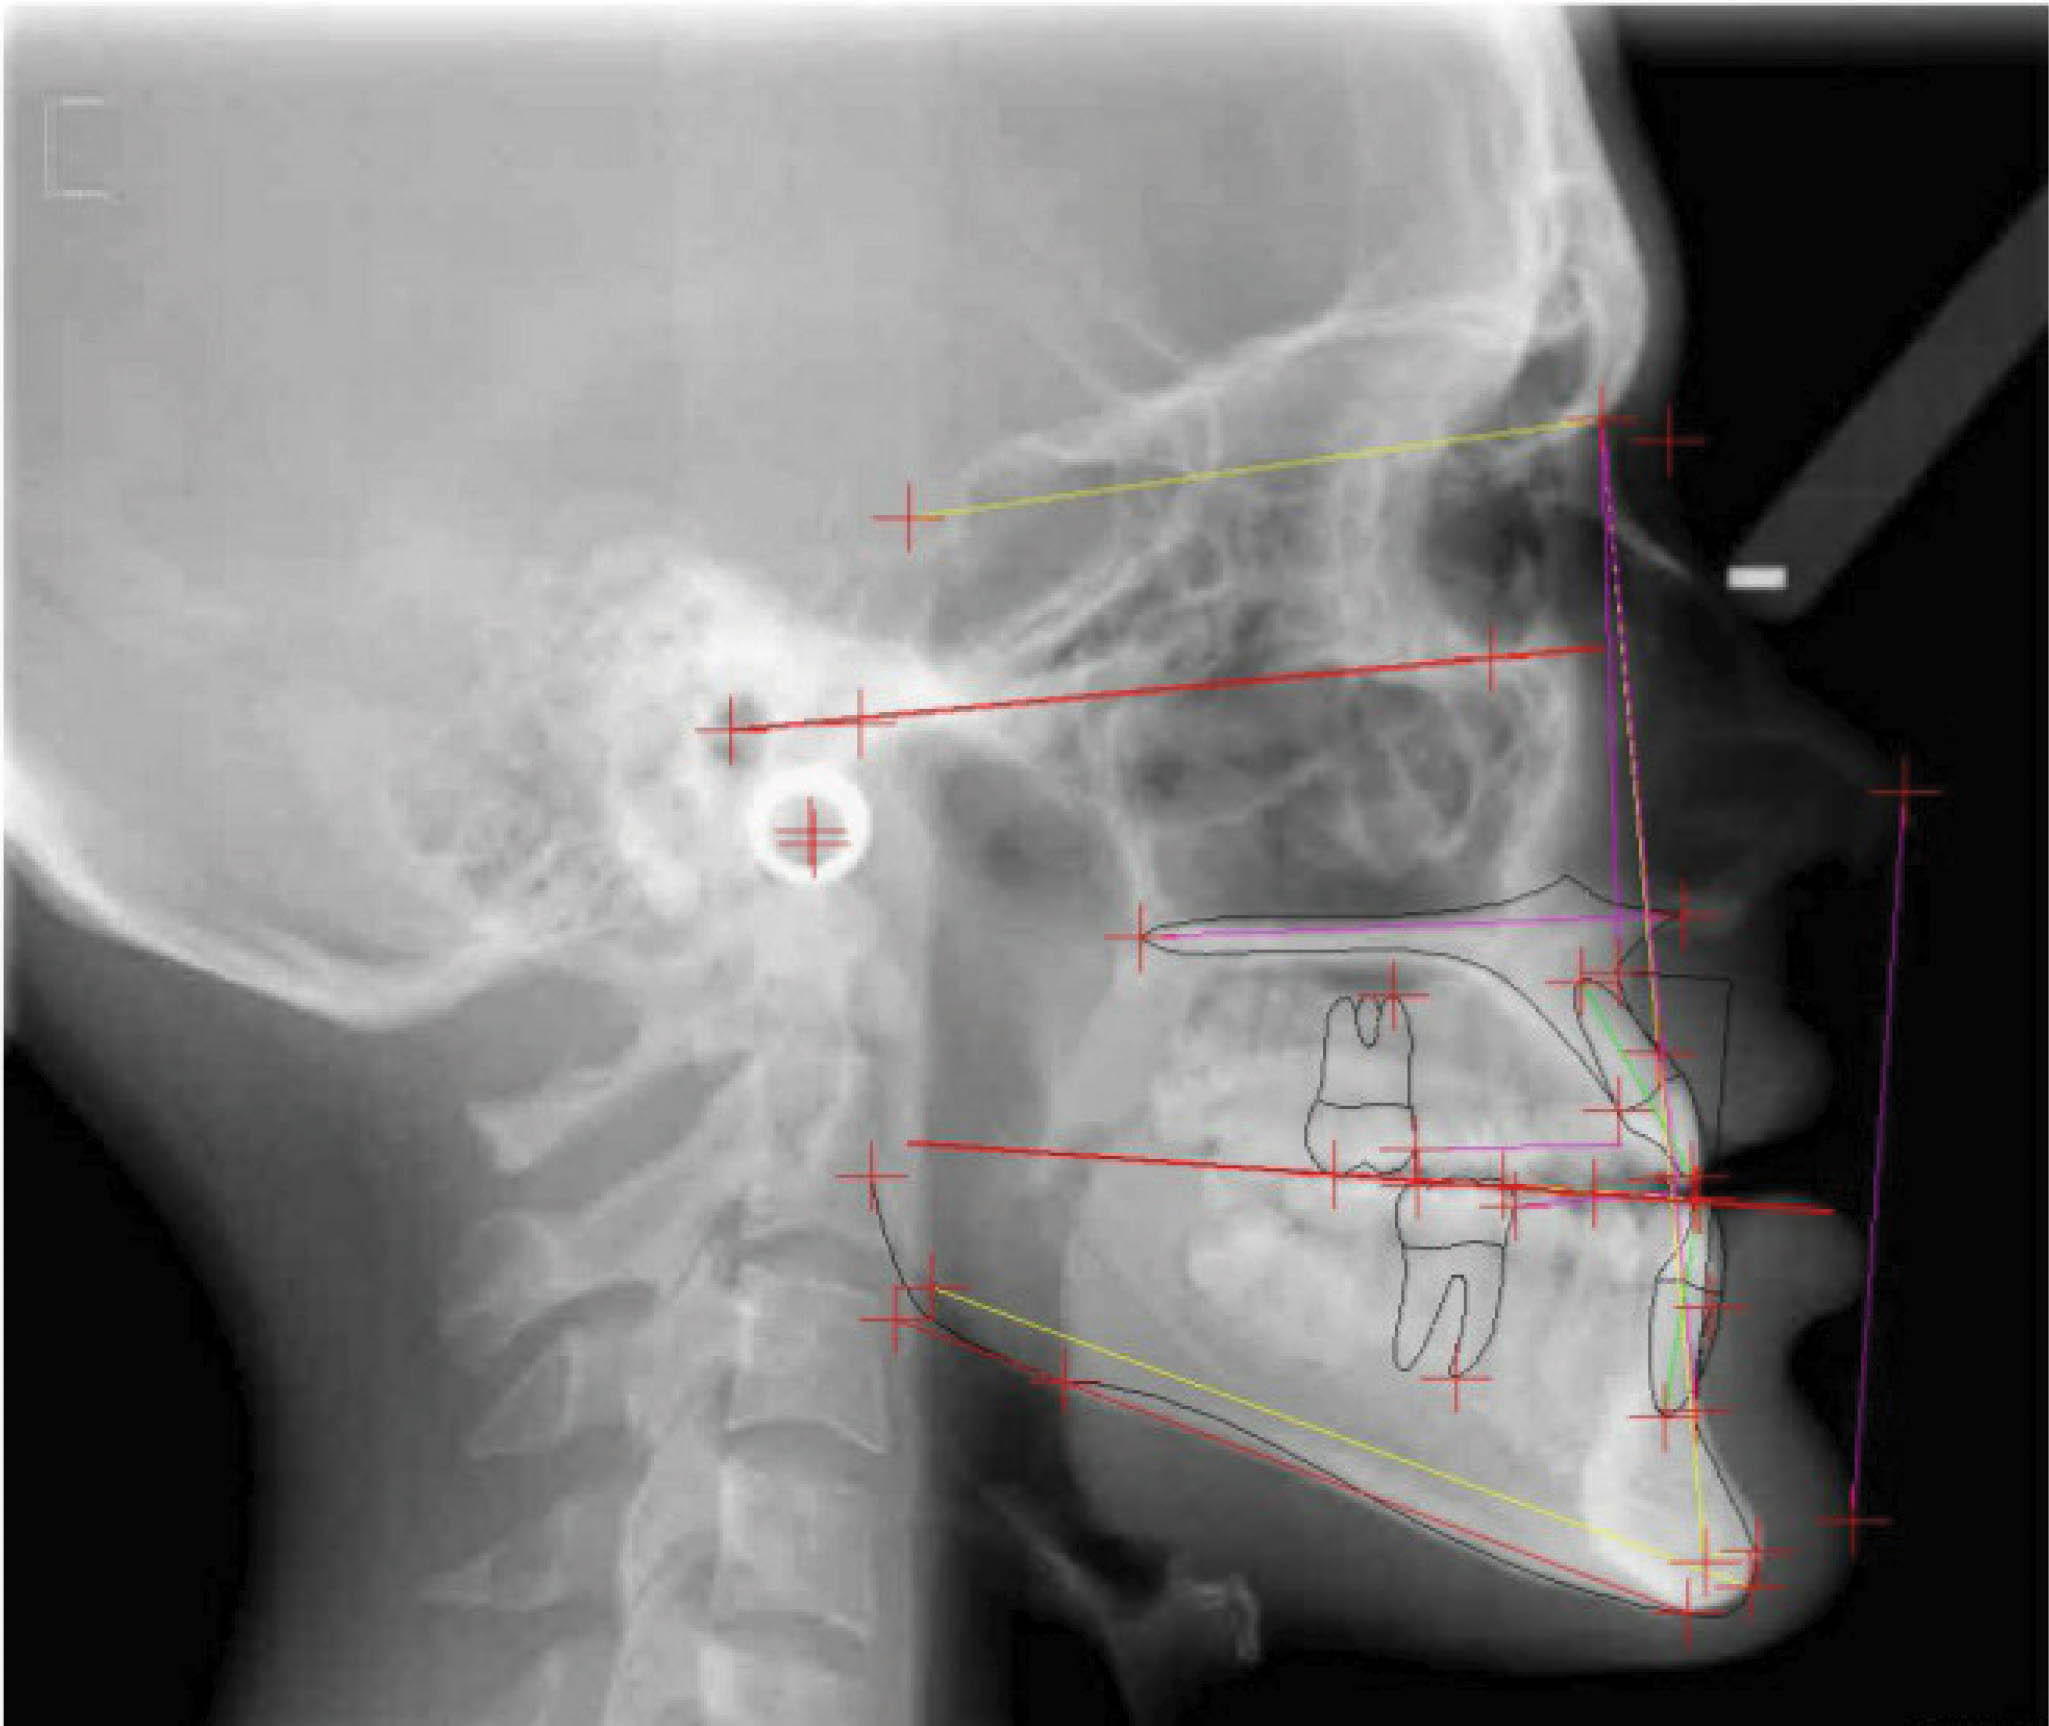

بیمار بعدی دختر ۱۲ ساله در مرحله اواخر میکس دنتیشن (شکلهای 92-۶ الی 94-۶) با اکلوژن ClII/1 است، دیپ بایت و کرادینگ دو فک دارد و لینگوالی شدن دندانهای قدامی بالا و پایین مشخص است. در (شکل 92-۶) هر دو لترال پایین را مشاهده میکنید که بلاک شدهاند. در OPG چیز خاصی مشاهده نمیشود و در لترال سفالومتری ارتفاع عمودی صورت کمی کاهش یافته و انسیزورها رترود شدهاند.

شکل 92-6

شکل 93-6

شکل 94-6